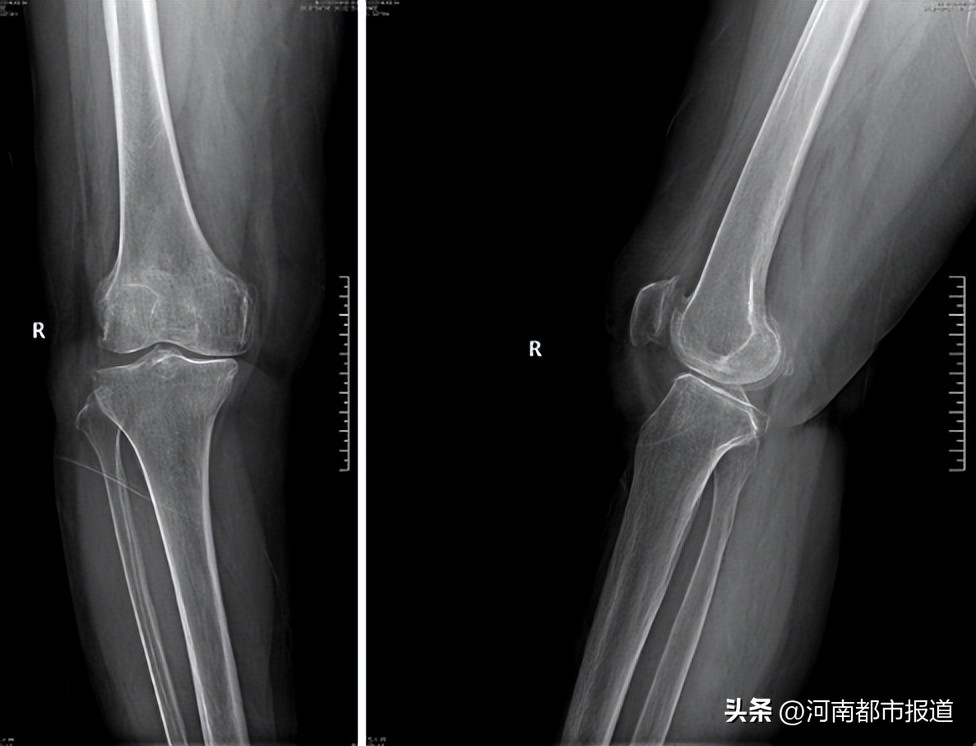

手术患者是一位60余岁的老年女性

膝关节前内侧疼痛

持续近10年

保守治疗无效

符合前内侧骨性关节炎的表现

针对此病人

郑州市骨科医院司文腾主任团队

决定为她行膝单髁置换术

AI-3D打印截骨导板辅助膝关节单髁置换术主要是通过术前获得患者双膝局部CT数据,导入软件三维重建双下肢骨骼全长,可在冠状面、矢状面精确测量下肢力线;术前软件设计截骨角度及截骨量,设计并打印出截骨导板,在术中辅助截骨。